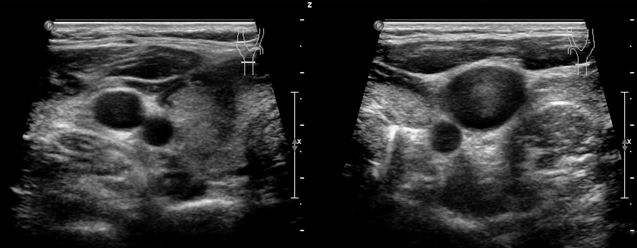

患者双侧颈内静脉张力较高,探头加压时管腔不易压瘪。

双侧颈内静脉失去受心脏搏动影响的搏动性频谱特征。双侧颈内静脉表现为连续带状血流频谱,流速降低,频谱形态略受颈总动脉搏动的影响。

双侧锁骨下静脉、颈外静脉和头臂静脉都为类似的连续低速带状血流频谱。